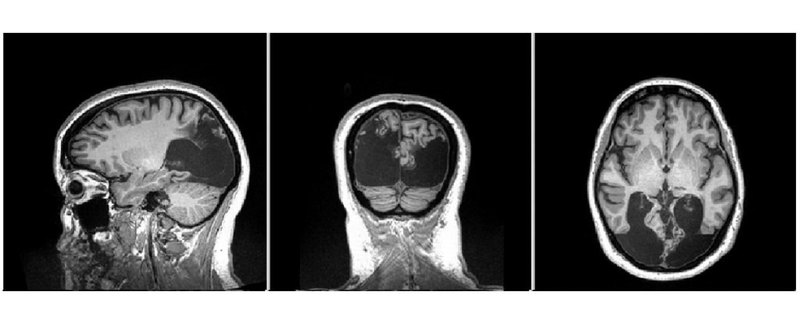

Синдром, как считают ученые, вызывается поражениями в затылочной доле — области

По словам Калхэм, у Каннинг в задней области